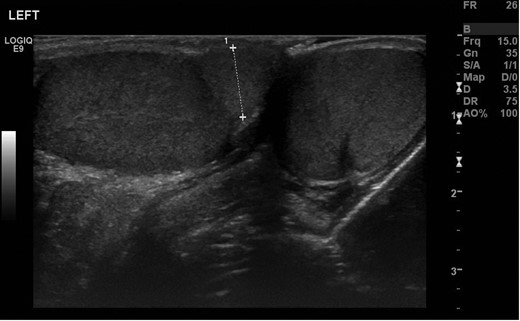

A 12-year-old boy was referred by his GP to the paediatric surgery clinic in a district general hospital with a 6-week history of a lump near the inferior pole of his left testicle. It was non-tender, non-erythematous and had not changed in size or consistency. He was otherwise fit and well, with no family history of urological disorders. On examination, his abdomen was soft and non-tender, with a normal right testis and right spermatic cord. A smooth well-defined lump was palpated on the inferior pole of the left testis. The rest of the testicle had a normal consistency with a normal left cord. Ultrasound demonstrated that both testicles were of a similar size, with normal vascularity and normal epididymi. The palpable lump corresponded to a well-defined 1-cm mass attached to the lower pole of the left testicle (Fig. 1). It had a similar echo pattern to the testicle with normal vascularity (Fig. 2), consistent with the finding of a bilobed testis.

Transverse ultrasonography of the scrotum. A mass is seen attached to the left testicle with the same echo pattern as the normal testicular tissue.